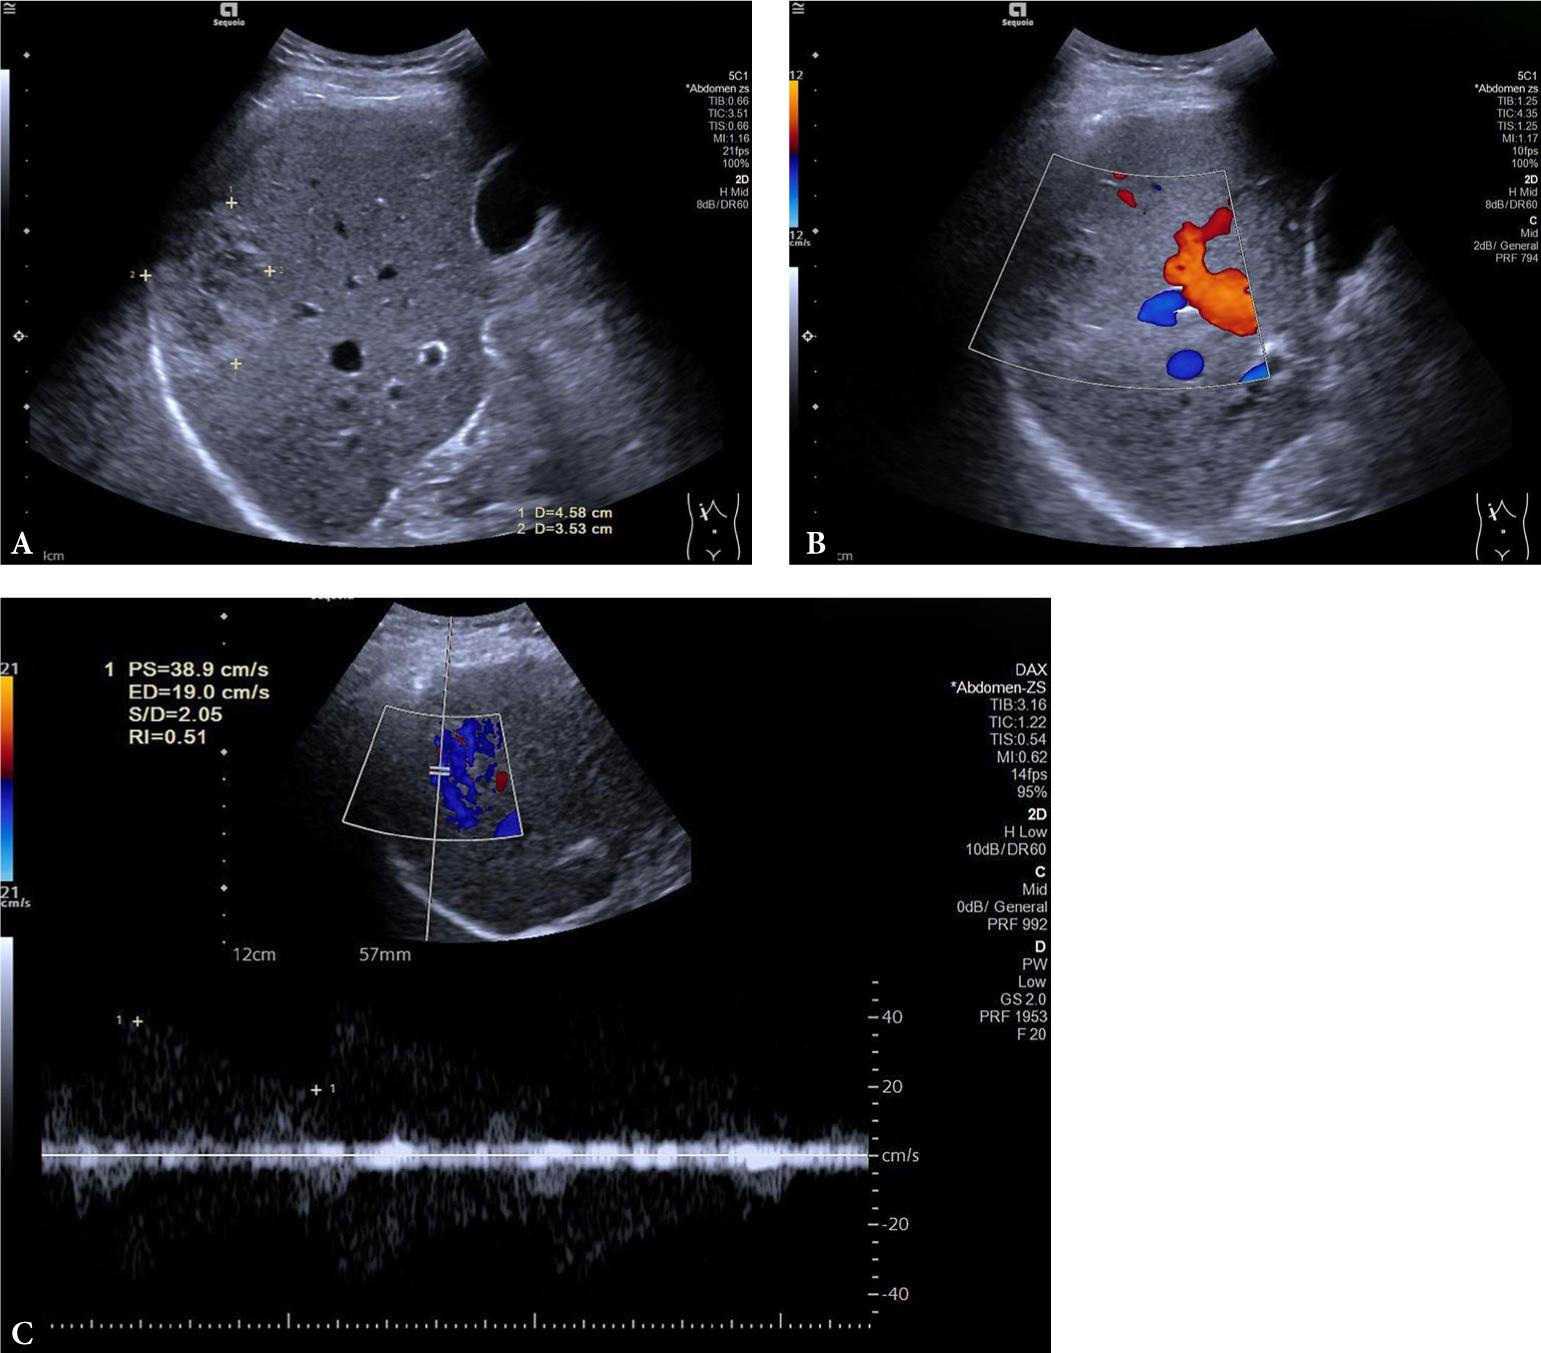

Fig. 4.